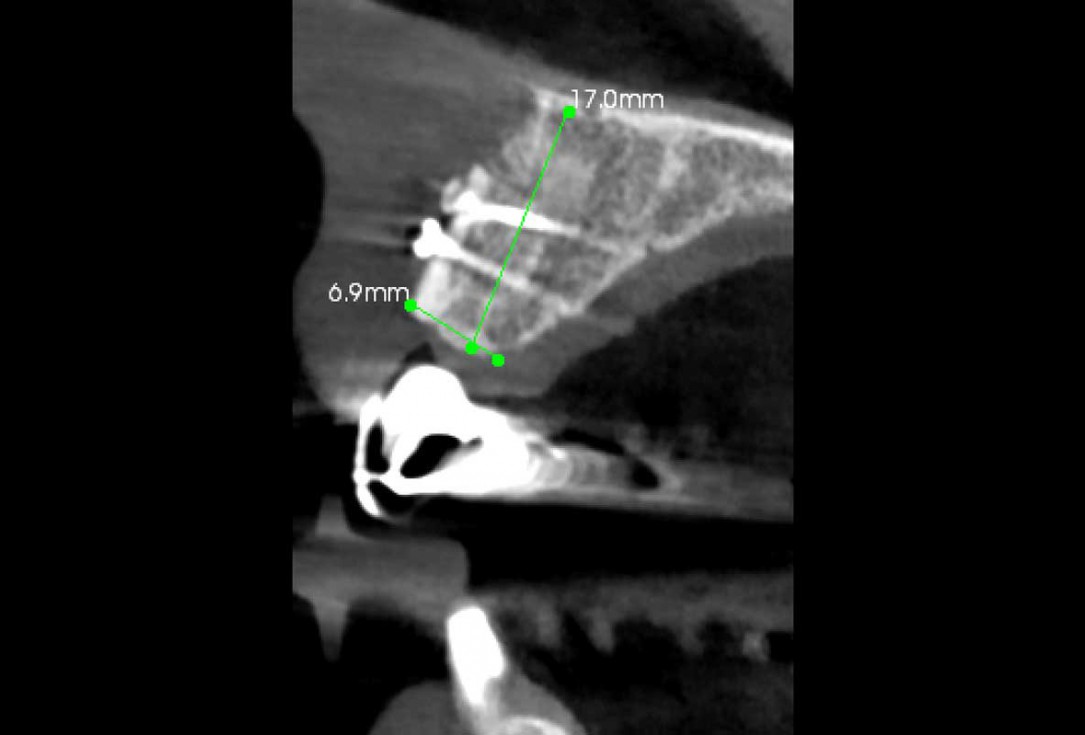

2/35 - Advanced bone loss after traumatic tooth loss more than 10 years agoBlock grafting in the aesthetic zone with maxgraft®, Jason® membrane and cerabone® - Dres. H. Maghaireh and V. Ivancheva

3/35 - CBCT: Advanced bone loss after traumatic tooth loss more than 10 years agoBlock grafting in the aesthetic zone with maxgraft®, Jason® membrane and cerabone® - Dres. H. Maghaireh and V. Ivancheva